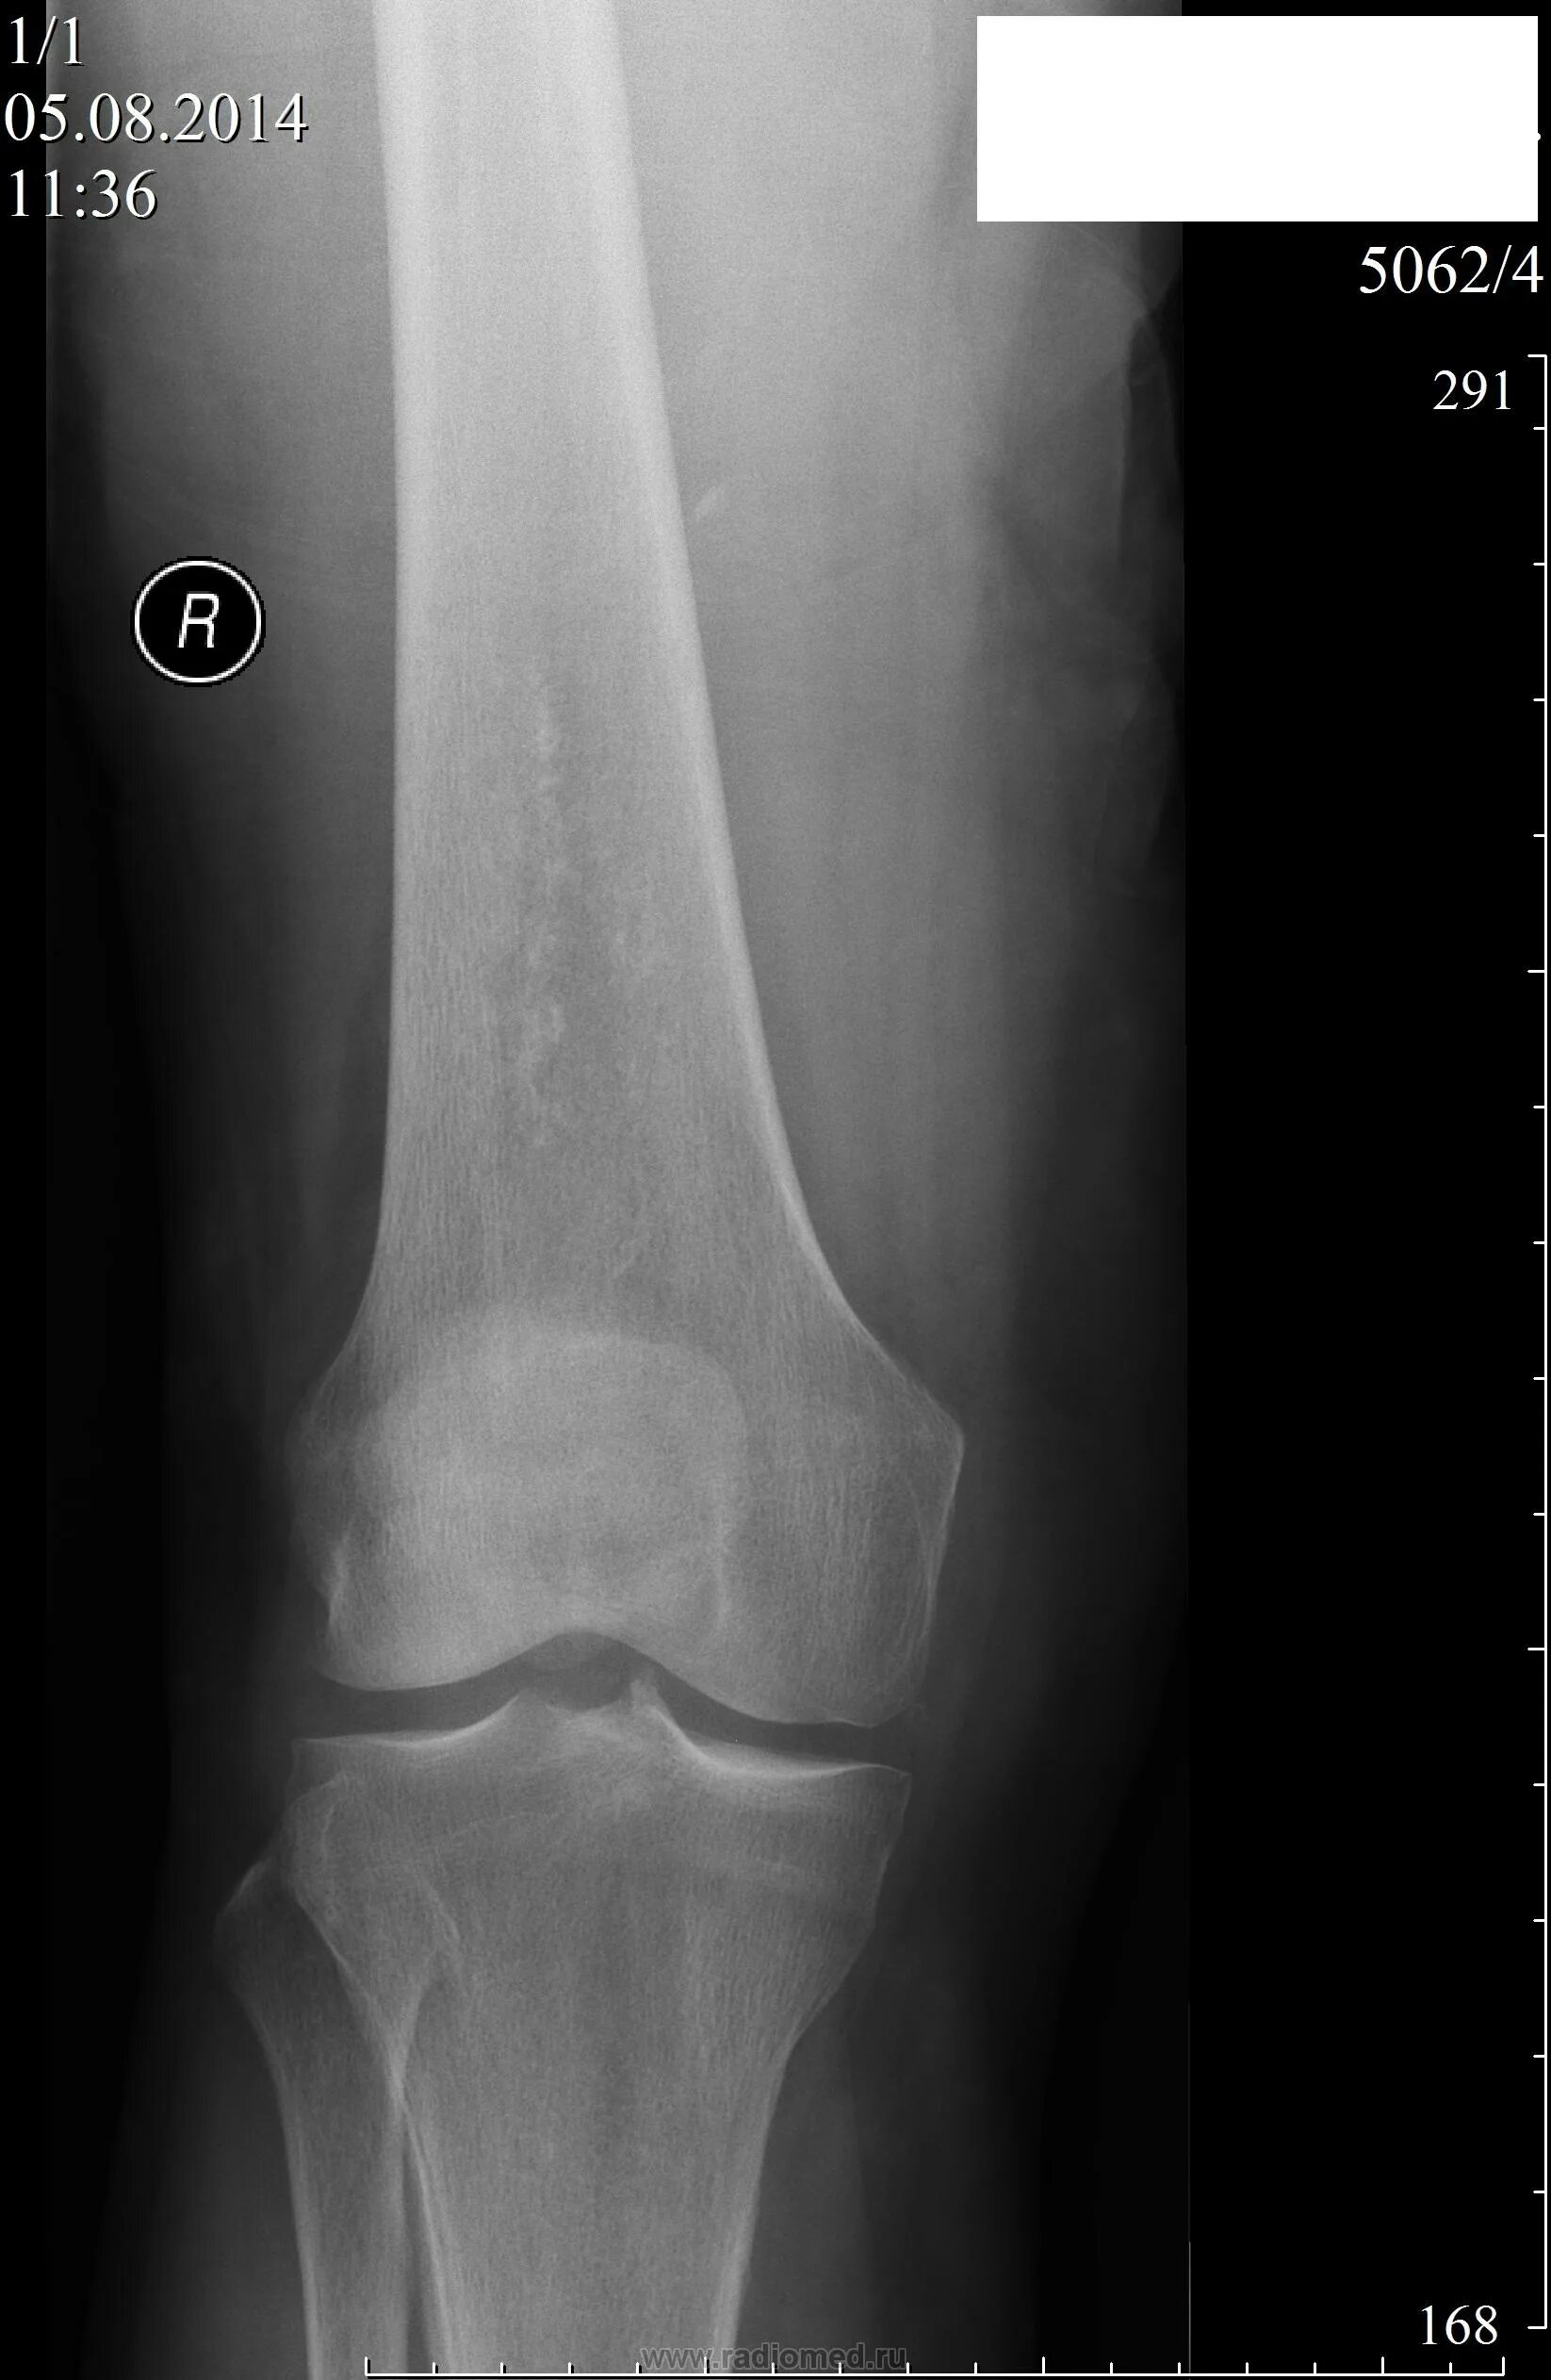

Обызвествление сухожилий мышц